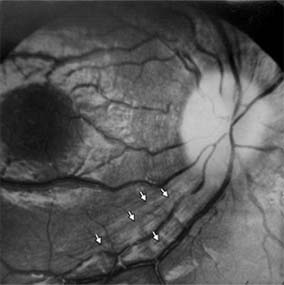

Figure 14-16

Figure 14-16: Atrophic papilledema in a child with a cerebellar medulloblastoma. The disk is pale and slightly elevated and has blurred margins. The white areas surrounding the macula are reflected light from the vitreoretinal interface. The inferior temporal nerve fiber bundles are partially atrophic (arrows).